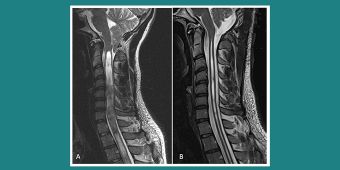

(A) Chiari I Malformation mit großer Syringomyelie bis in die Brustwirbelsäule. (B) 3 Monate nach Dekompression des Foramen Magnum mit Duraerweiterung sind die Kopfschmerzen verschwunden und die Syringomyelie deutlich rückläufig

(A) Syringomyelie von HWK4 bis BWK8 durch eine das Rückenmark von hinten komprimierende Arachnopathie bei BWK8/BWK9. (B) 4 Monate nach Entfernung der Arachnopathie erkennt man ein völliges Verschwinden der Syringomyelie bei Erhalt der neurologischen Funktionen und Besserung der Mißempfindungen